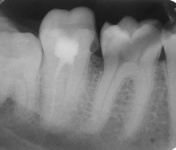

И обязательными при диагностике заболеваний и лечении зубов будут так называемые«прицельные» снимки. Правильное название данного метода - интраоральная рентгенография зубов. Эти снимки проводятся для определения состояния костной ткани возле апекса (верхушки) корня и в процессе лечения для контроля расположения эндодонтического инструмента в корневых каналах и контроля качества пломбирования корневых каналов. Кроме того, интраоральные рентгенограммы, проведенные по интерпроксимальному методу, показывают состояние коронковой части зуба: наличие кариозной полости на контактных поверхностях коронковой части и пришеечных отделах зубов, а также на пришеечных и жевательных поверхностях коронковой части зуба под реставрацией (пломбами и металлокерамическими конструкциями), наличие твердого зубного налета («камушки»), качество прилегания реставрации.